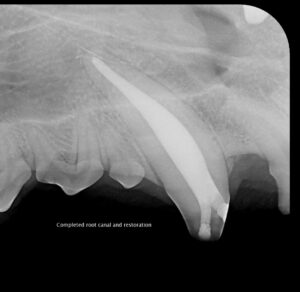

- Root canal therapy (endodontic treatment): We remove infected or dead pulp, thoroughly clean and seal the root canal system, and restore the tooth with a filling or crown. This is often the preferred choice for preserving important teeth and maintaining function.

Our team uses state-of-the-art diagnostics and gentle techniques to ensure your pet’s comfort throughout treatment. Before-and-after photos illustrate the clinical and radiographic results of a successful canine tooth root canal, showing how we can preserve and restore teeth to full function.